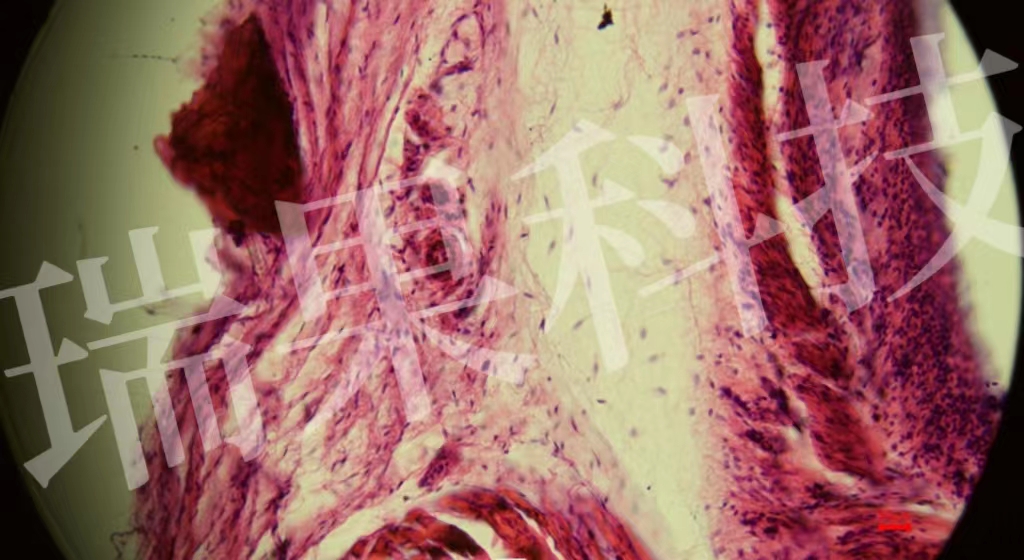

HE染色:蘇木精 - 伊紅染色法 ( hematoxylin-eosin staining ) ,簡(jiǎn)稱(chēng)HE染色法 ,石蠟切片技術(shù)里常用的染色法之一 。蘇木精染液為堿性 ,主要使細(xì)胞核內(nèi)的染色質(zhì)與胞質(zhì)內(nèi)的核酸著紫藍(lán)色 ;伊紅為酸性染料 ,主要使細(xì)

HE染色:蘇木精 - 伊紅染色法 ( hematoxylin-eosin staining ) ,簡(jiǎn)稱(chēng)HE染色法 ,石蠟切片技術(shù)里常用的染色法之一 。蘇木精染液為堿性 ,主要使細(xì)胞核內(nèi)的染色質(zhì)與胞質(zhì)內(nèi)的核酸著紫藍(lán)色 ;伊紅為酸性染料 ,主要使細(xì)胞質(zhì)和細(xì)胞外基質(zhì)中的成分著紅色 。HE染色法是組織學(xué)、胚胎學(xué)、病理學(xué)教學(xué)與科研中最基本、使用最廣泛的技術(shù)方法。